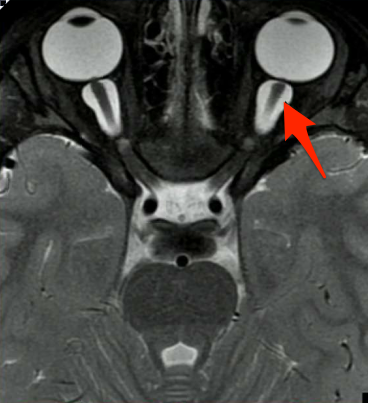

What structure is indicated in the T2 image below?

Middle cerebellar peduncles. Note that most of the white matter (which is dark on FLAIR) from the MCP makes up the core of the cerebellum.